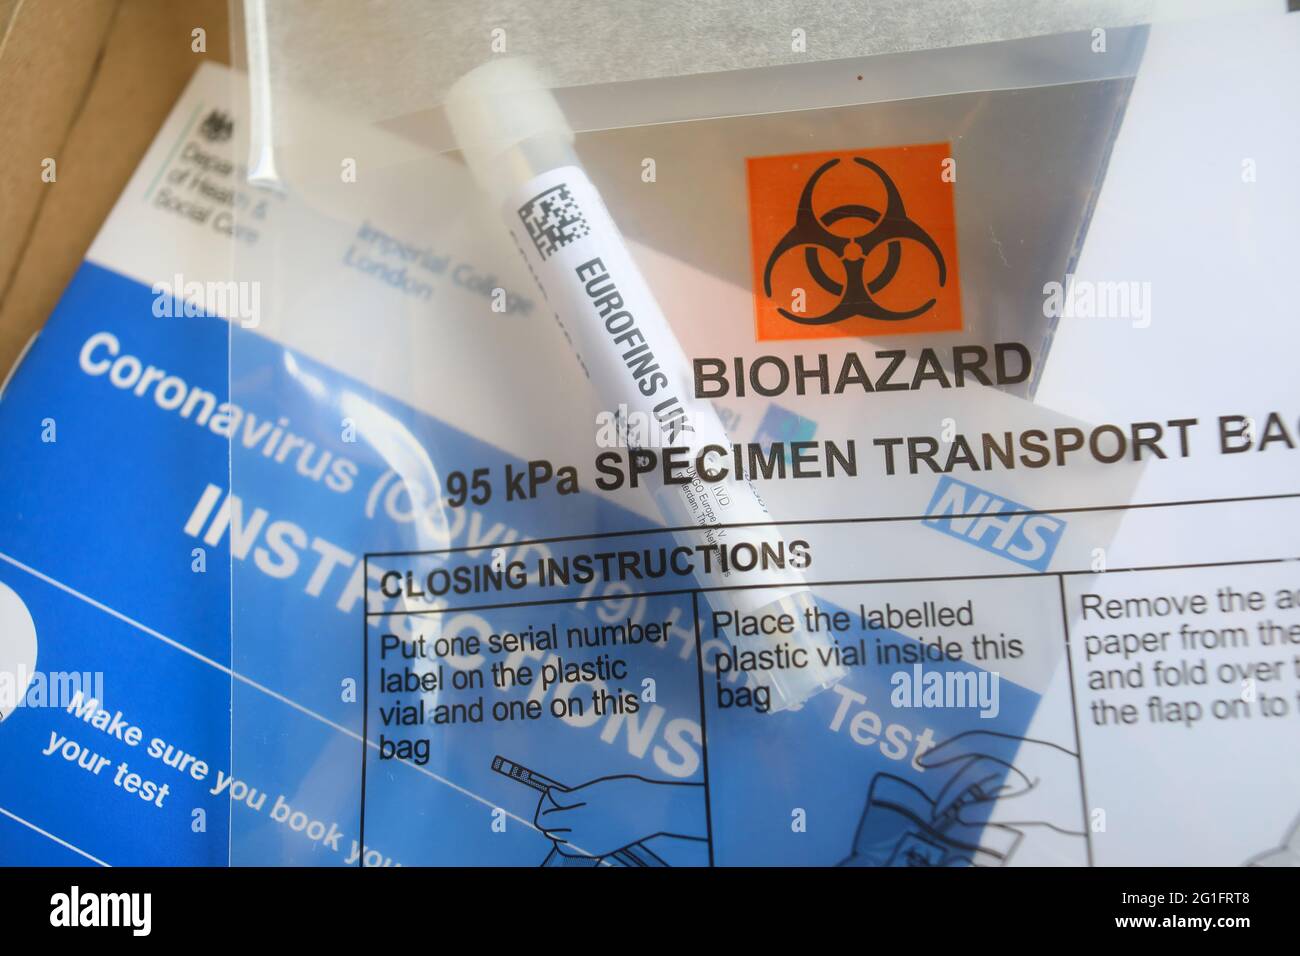

PCR at home test, UK Stock Photohttps://www.alamy.com/image-license-details/?v=1https://www.alamy.com/pcr-at-home-test-uk-image431221852.html

PCR at home test, UK Stock Photohttps://www.alamy.com/image-license-details/?v=1https://www.alamy.com/pcr-at-home-test-uk-image431221852.htmlRM2G1FRTC–PCR at home test, UK

PCR at home test, UK Stock Photohttps://www.alamy.com/image-license-details/?v=1https://www.alamy.com/pcr-at-home-test-uk-image431221846.html

PCR at home test, UK Stock Photohttps://www.alamy.com/image-license-details/?v=1https://www.alamy.com/pcr-at-home-test-uk-image431221846.htmlRM2G1FRT6–PCR at home test, UK

PCR at home test, UK Stock Photohttps://www.alamy.com/image-license-details/?v=1https://www.alamy.com/pcr-at-home-test-uk-image431221848.html

PCR at home test, UK Stock Photohttps://www.alamy.com/image-license-details/?v=1https://www.alamy.com/pcr-at-home-test-uk-image431221848.htmlRM2G1FRT8–PCR at home test, UK